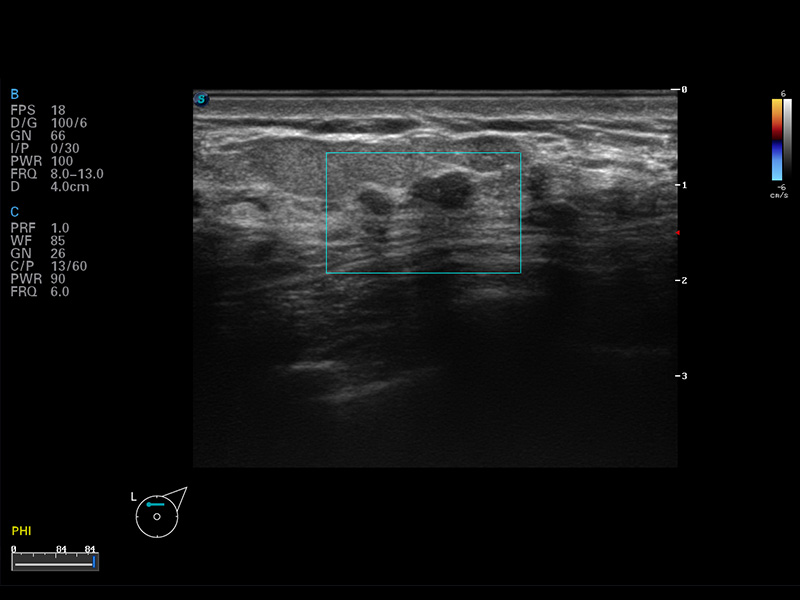

S8 EXP便携式彩色多普勒超声诊断仪是哈哈体育官网研发的高端全身应用型便携彩超。高通道的VIS平台融合可视化(Visual)、智能化(Intelligent)和人性化(Smart)的特点,配以哈哈体育官网自主研发生产的探头大家族,使您能够快速、准确的获得病人信息,提高工作效率的同时减轻疲劳。

μ-Scan微米成像